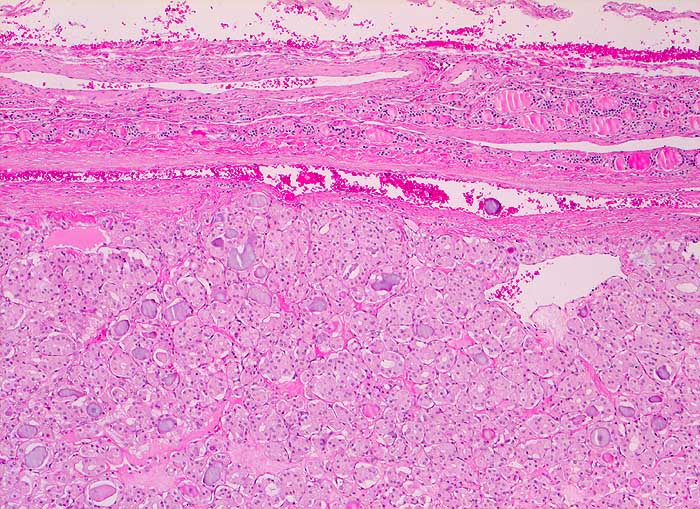

Mikrofollikuläres Schilddrüsenadenom (toxisches Adenom)

Scharf begrenzter Knoten mit schmaler Kapsel. Ausserhalb des Knotens atrophes Schilddrüsenparenchym. Das Adenom besteht aus kleinen Follikeln mit hochprismatischem aktiviertem Epithel. Die Follikel enthalten wenig oder gar kein Kolloid.

Makroskopisch solitärer bunter Knoten von 6cm Durchmesser.

Zytologisch wurde aufgrund der zahlreichen vorhandenen Epithelien und einzelner Mikrofollikel eine follikuläre Neoplasie diagnostiziert.